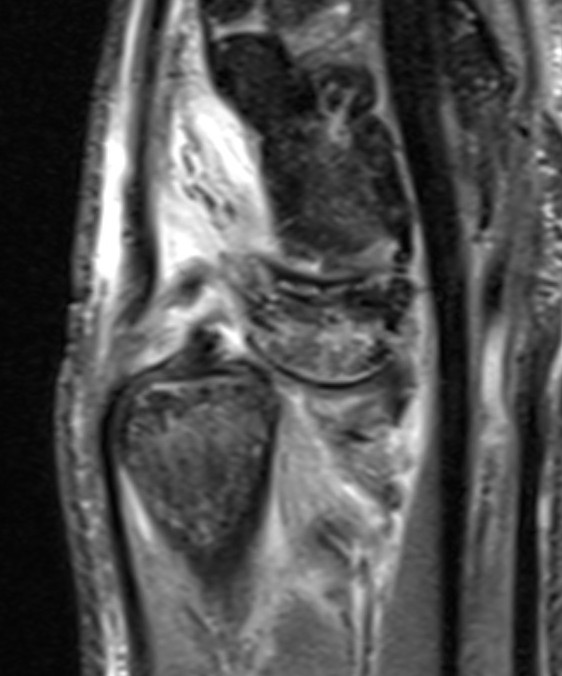

Ulna styloid process fracture and acute DRUJ instability

Ulna styloid fracture with TFCC injury